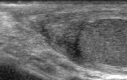

Scrotal trauma accounts for less than 1% of all trauma-related injuries. Traumatic injuries of the epididymis are extremely rare.Here we report a rare case of hematoma of the epididymis, diagnosed with US, in a 10-year-old boy after a sport injury.